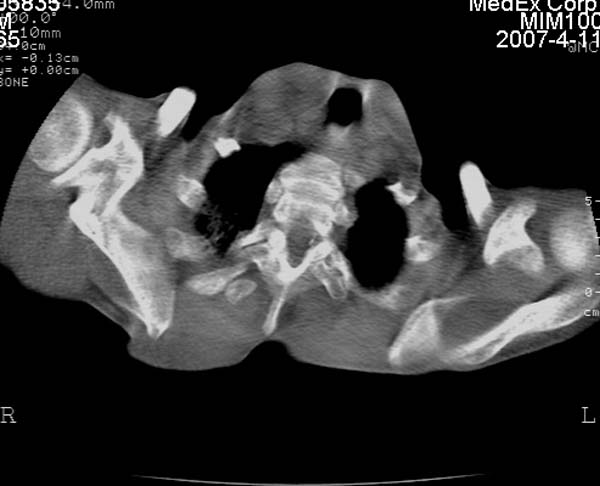

以下是引用zhangzhongshou在2007-4-12 17:21:00的发言:[br]1慢性支气管炎,肺气肿[br]2、肺源性心脏病[br]3、胸廓畸形[br]4、心衰并肺泡型肺水肿(双肺蝶翼征)[br]5、未见肺栓塞表现